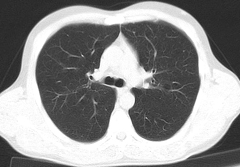

Сделать томографию легких можно в двух режимах: оценить состояние легких и органов средостения: трахеи, сердца, верхней полой вены, лимфатических узлов, легочной аорты и артерии.

С помощью томографии можно выявить хроническую эмболию, туберкулез, диффузные заболевания, рак легких (локализация опухолей, состояние лимфоузлов, наличие и распространенность метастаз), пневмонию, профессиональные заболевания, вызванные вдыханием кремниевых частиц, асбеста, кварца и т.п.